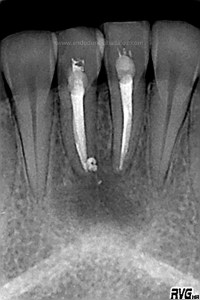

Frente al tratamiento puramente endodóntico, las piezas presentaban vitalidad negativa, fueron tratadas en dos sesiones, rellenando el conducto con Hidróxido de Calcio: